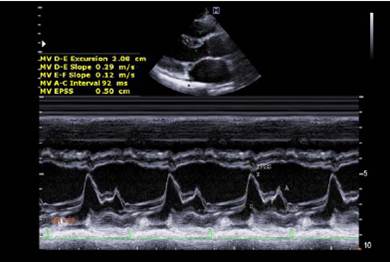

Який режим роботи УЗ-апарату зображено на рисунку?